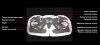

- Axial section

Axial T1 large field of view allows for evaluation of both hips simultaneously, particularly the acetabulae.

Axial PD fat suppressed is sensitive to fluid that may be present with avascular necrosis or stress fractures, while maintaining high a SNR.